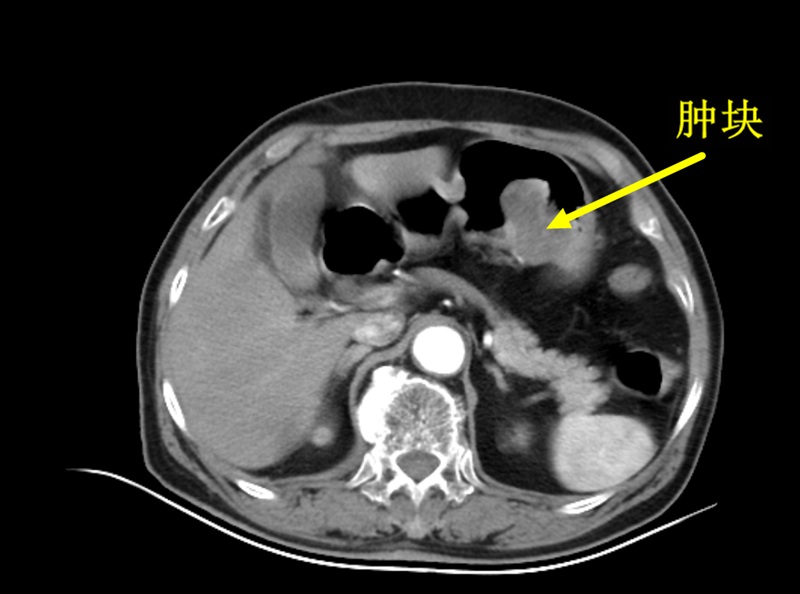

让她没想到的是,医生根据胃镜及影像学检查,胃部有一个5cm大小肿块,初步诊断:胃间质瘤可能,需要手术治疗。

张宝杭主任介绍,间质瘤好发于胃肠道,是最常见的间叶源性肿瘤,以胃、小肠最为多见。临床表现无特异性,肿瘤较小可无任何症状,随着肿瘤的增大,可表现为恶心、呕吐、上腹胀痛、贫血、腹部肿块与消化道出血等。

胃肠道间质瘤因其非特异的临床表现,给早期诊断带来一定困难。胃间质瘤的发现可能因体检或出现以上消化道症状而经胃镜检出,结合CT、等影像检查、超声内镜等,做出临床诊断。